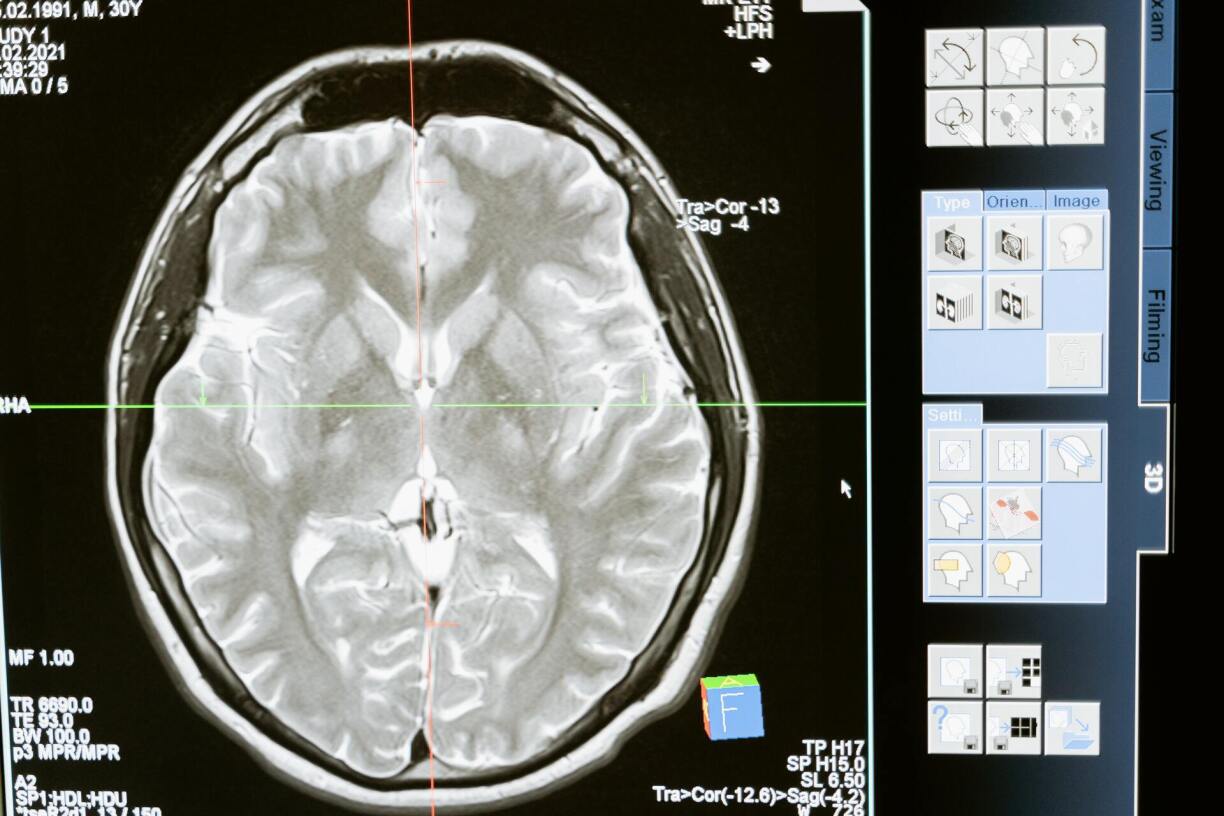

The truth is that the answer is in the word itself. Mental comes from Latin mentalis, which means ‘of the mind’. Most of the advice we are given are actions targeting our mind’s activity. That is to say that a major part of our well-being is no other than in our own brain.

Despite the misconception, the brain is not entirely logical. Throughout its evolution, it developed new structures in charge of different functions. These structures now make the brain home to various processes, ranging from logic and cognition to imagination and creativity.

However, that does not mean they cannot change. The brain is elastic, and our brain’s wiring can be modified. It is a change of mindset, which can be hard, but the reward is the improvement of your mental health.

Emotional intelligence is, in a very simple way, our ability to understand and manage emotions. It also includes how this ability, or lack thereof, impacts our relationships, not only with others but also with ourselves. Empathy, motivation, social skills, and self-awareness are just some of the qualities to work on to better our emotional intelligence. And all these qualities are based on the brain.

The emotional part of our heads and the logical part are constantly communicating. And as a result of their interactions, we create actions that align with our feelings and are also adequate to the situation. It is a way of not letting us get too wrapped up in our emotions, especially the negative ones.

But we can always strengthen the connection. Given that, as previously mentioned, the brain is elastic, emotional intelligence can be worked on and improved. Therefore, when in a bad mental state, we can still try and cultivate our emotional well-being.